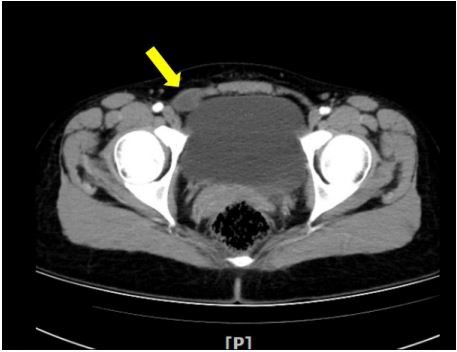

Figure 3: CT: Cystic lesions are seen in the lower right abdomen and groin area (the yellow arrow).